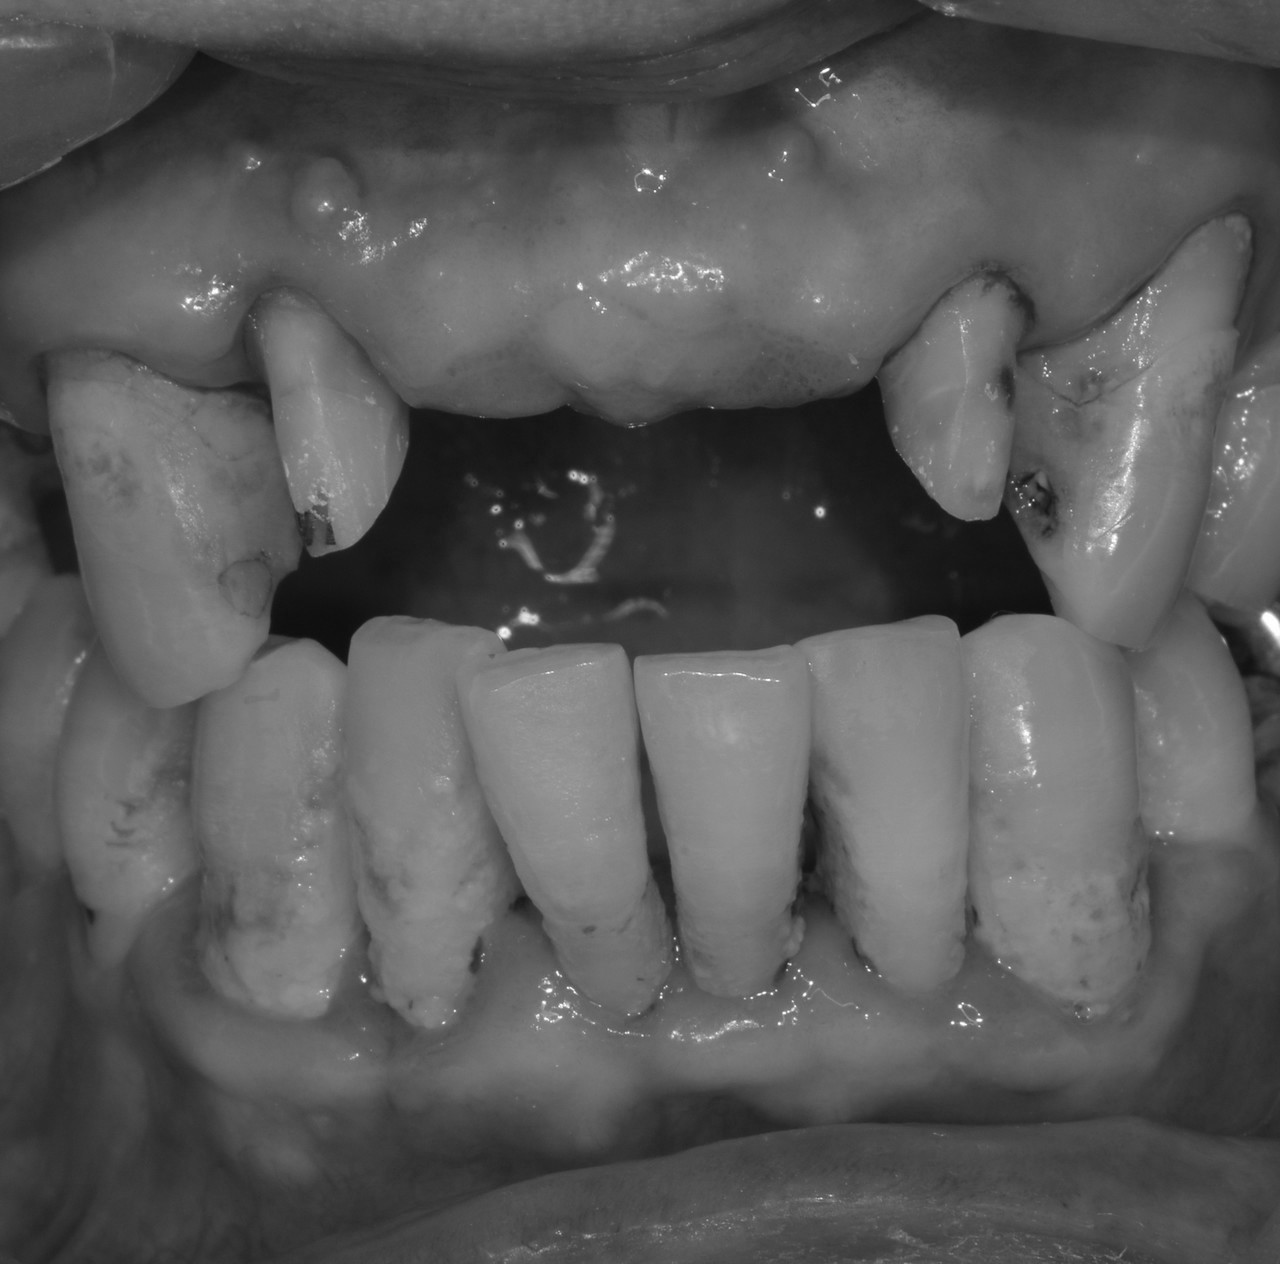

치아우식, 신경치료 및 치은성형술, 심미보철치료

치료 기간 2023. 11. 02 ~ 2023. 12. 20

확장 개원 후 마무리하신 환자분입니다. 앞니 기존 보철물을 하고 계셨지만 치아가 삭아서 보철물이 탈락해서 내원하셨습니다. 환자분께서는 뽑고 임플란트를 생각하고 오셨지만...

“치아는 살릴 수 있다면, 살리는 게 좋다.”

간단한 잇몸 수술, 신경치료 후에 기둥을 세워 치아머리만 만들어진다면 충분히 살릴 수 있다고 판단하고 살리는 쪽으로 설명드렸습니다. 환자분들의 치아 하나하나를 소중히 생각하는 참조은치과입니다.

* 상기 사진은 본원 권대근 대표원장이 치료한 환자분의 동의를 받은 이미지 사진으로 실제와 차이가 있을 수 있습니다.